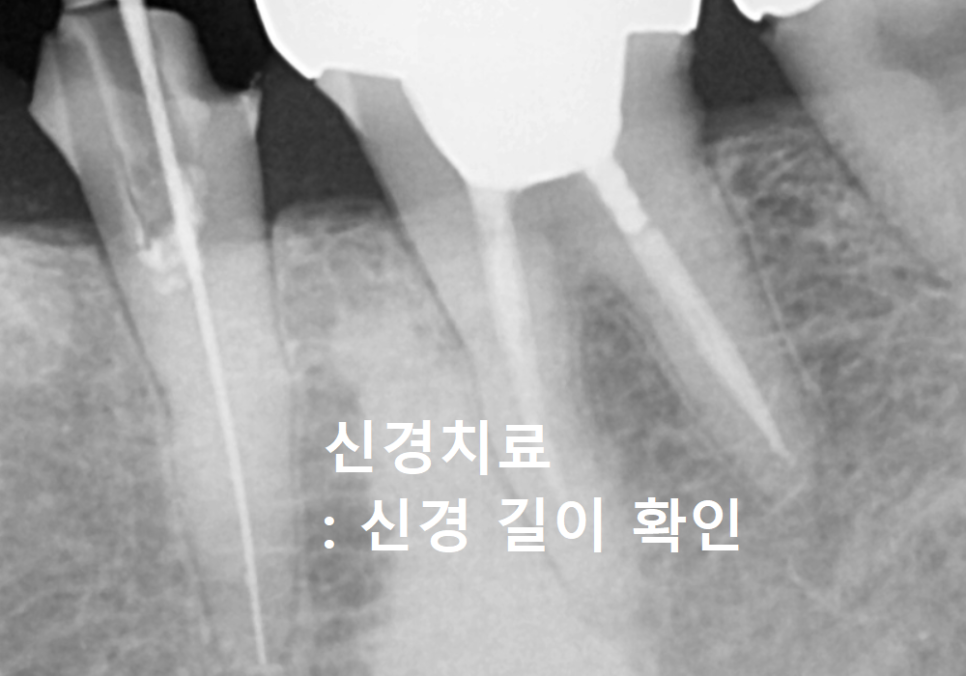

다행히 뿌리 쪽에 염증은 보이지 않아서,

신경치료를 하고 크라운을 씌워

다시 한번 튼튼하게 써보실 수 있도록

환자분과 충분히 상의를 했었는데요.

다만, 치아가 부러질 때의 충격 때문에

뿌리 쪽에 눈에 보이지 않는

'미세한 금(Crack)'이 갔을 가능성도 있어서,

그 부분에 대해 꼼꼼히 설명해 드렸습니다.

혹시라도 정성껏 치료를 마쳤는데도

통증이 남는다면, 그때는 부득이하게

발치를 해야 할 수도 있다는 점도

조심스럽게 미리 말씀드렸어요.

하지만 너무나 안타깝게도 치료 후에도

식사하실 때마다 울리는 듯한 통증이

가라앉지를 않았습니다.ㅜㅜ

결국 우려했던 뿌리 쪽 금이

원인인 것으로 판단되어,